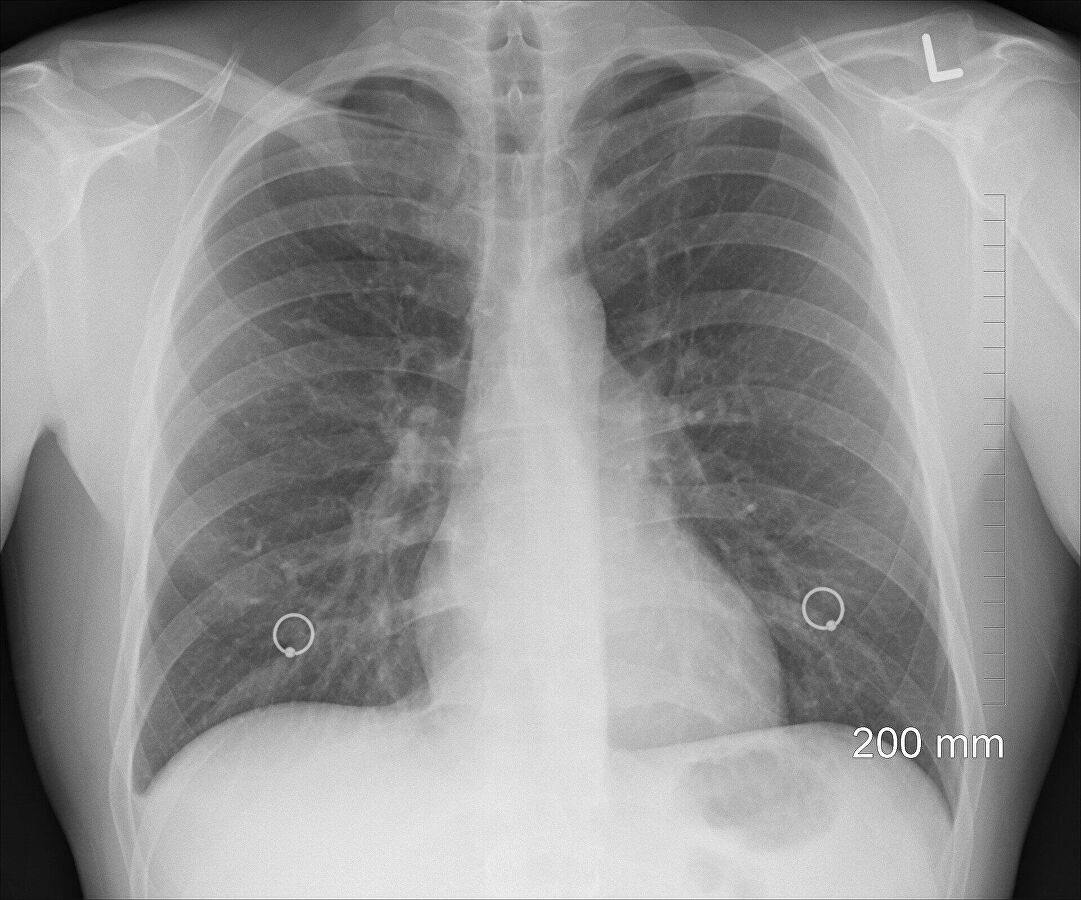

Sie sind hier: Startseite Nachrichten Gesundheit Lungenfunktion bei jungen Erwachsene nach Covid-19 nicht eingeschränkt Lungen (Symbolbild)

Lungen (Symbolbild)

Bild: © CC0 / oracast / Pixabay